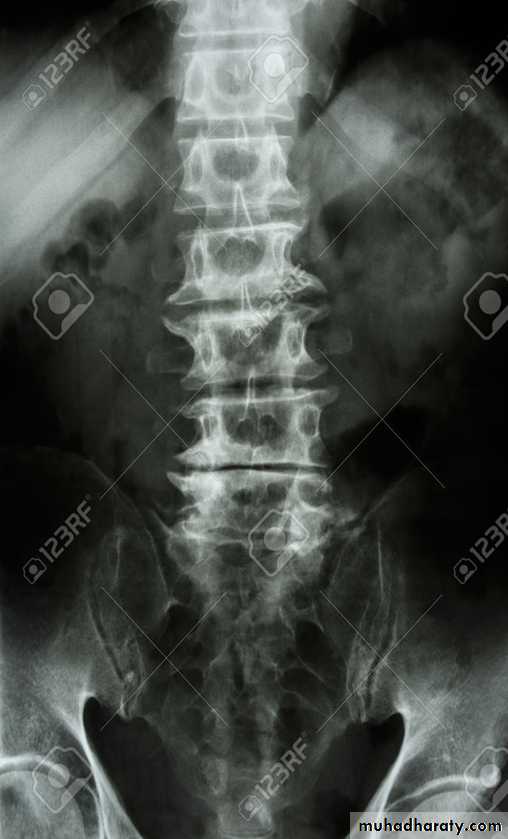

In the Spine :

* Lower cervical and low lumbar spine are most comonly affected.* Osteophytes may encroach on neural foramina (best seen on oblique views).

*Vacuum phenomenon: gas (N2),is pathognomonic of the degenerative process.

* OA of the spine occurs in the apophyseal joints .

* Degenerative spondylolisthesis (pseudospondylolithesis)

Lumbar spondylosis. There is distal narrowing and a vacuum

phenomenon is present in the degenerative discs. Marginal osteophytes arepresent. Inferiorly the facet joints show features of degeneration and, with the increase in lordosis, the spinous processes are in contact